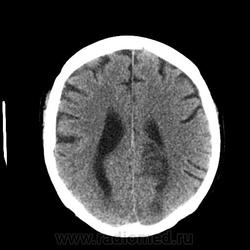

Уважаемые коллеги. Столкнулся с неоднозначной картиной при КТ головного мозга. Анамнез: мужчина с опухолью мочевого пузыря потерял сознание, сколько был без него - не знает, когда пришел в себя - "ослеп". Проведена КТ головного мозга с внутривенным "усилением". Чем могут быть, на ваш взгляд, обусловлены гиподенсивные зоны - метастазами или чем-то другим? Смущает, что нет типичного для метастаза феномена накопления контрастного вещества, да и вообще картина не характерная для них, на мой взгляд. Вот здесь http://files.mail.ru/67D10D5A26D74E27A6B5C2BFC12E9706 выложены две папки (нативное и с "усилением"), в которые упакованы изображения в формате dicom. Какие будут предположения? Благодарю за внимание. Нажимаем "читать далее"!

жаль что не весь объем вы выложили. по мне так похоже на mts. можно конечно предположить, что какой нибудь опухолевый тромб стрельнул в голову, произошла ишемия и развился ишемический инсульт, но не слишком похоже...

Как дилетант в кт отмечу, что в бассейны не вмещается инфаркт.

И смущает симметричность " метастазирования", это отек, но метастатический ли..